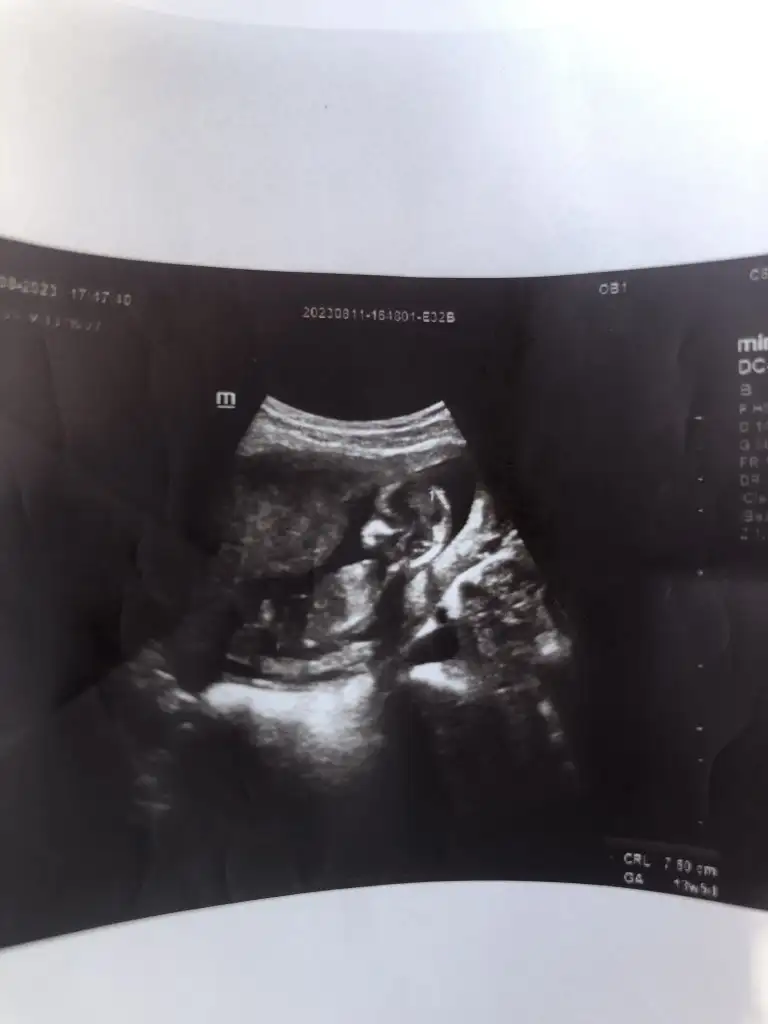

Kıza benziyorBen hala nub teorisi cözemenlerdenimbanada cinsiyet tahmini yapabilirmisiniz lutfenEki Görüntüle 3277912

Ben hala nub teorisi cözemenlerdenimbanada cinsiyet tahmini yapabilirmisiniz lutfenEki Görüntüle 3277912

O bir kız bebekBen hala nub teorisi cözemenlerdenimbanada cinsiyet tahmini yapabilirmisiniz lutfenEki Görüntüle 3277912